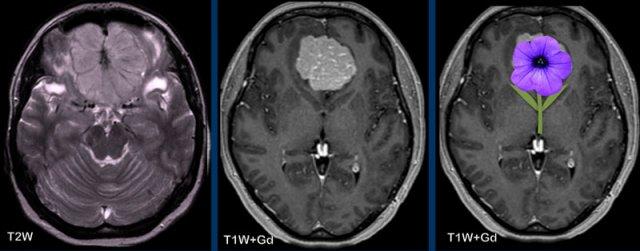

Các hình ảnh này của một phụ nữ 63 tuổi mắc bệnh von Hippel-Lindau.

Hãy quan sát kỹ. Dấu hiệu nào khó nhận thấy?

Hình ảnh

Có một nang lớn với một nốt nhỏ ngấm thuốc ở bán cầu tiểu não phải.

Thành nang không ngấm thuốc.

Lưu ý nốt u nằm ở phía màng mềm (mũi tên).

Có thêm hai nốt nhỏ ngấm thuốc ở mặt sau của tiểu não.

Đa u hầu như luôn liên quan đến bệnh von Hippel-Lindau.

Các hình ảnh này của một nam giới 29 tuổi.

Tổn thương dạng nang với thành không ngấm thuốc và một nốt ngấm thuốc nằm ở phía màng mềm.

Kết luận

Hình ảnh điển hình của u nguyên bào mạch máu.

Khi phẫu thuật cắt bỏ khối u này, phẫu thuật viên chỉ cần lấy bỏ phần nốt.